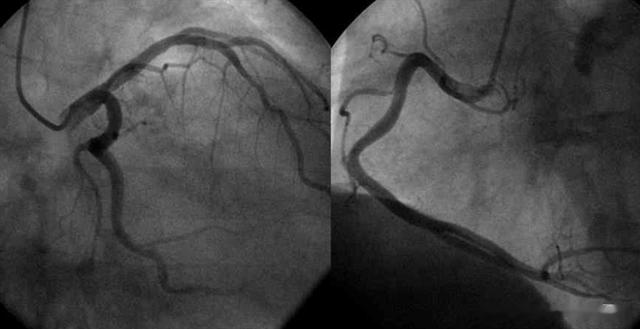

结果显示 , 刘先生白细胞 (WBC) 为5.8×10^9/L , 低密度脂蛋白胆固醇(LDL-C)180mg/dL , 肌酐(CR)为74umol/L , 谷丙转氨酶(ALT) 34U/L , 肌酸激酶同工酶 (CK-MB) 1.2ng/ml;心电图结果显示存在轻微的ST段改变;冠状动脉造影结果显示心脏冠状动脉存在明显的斑块 , 并且狭窄程度达到了50% 。结合以上实验室及影像检查结果 , 刘先生被确诊为心脏冠状动脉斑块诱发的冠心病 。 由于他曾经出现过类似症状 , 医生建议可以考虑手术装个支架 , 也可以药物和改变生活习惯进行干预 , 经过慎重考虑 , 刘先生及家人还是选择了后者 , 先保守治疗 。

经过一年的积极治疗和严格遵循医生的建议 , 刘先生再次来到医院接受复查 。 结果显示他的各项健康指标均取得了显著的改善 , 其中血脂控制尤为出色 , LDL-C水平成功降低至105mg/dL;冠状动脉造影检查显示 , 狭窄程度已经从原先的50%大幅下降至10% 。